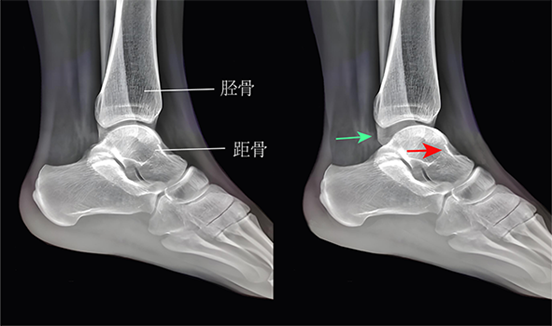

▶距腓前韧带断裂时,抽屉试验(+),距骨前移。

距腓前韧带断裂时,抽屉试验可见距骨前移(右图,红色箭头),踝关节间隙增宽(绿色箭头)